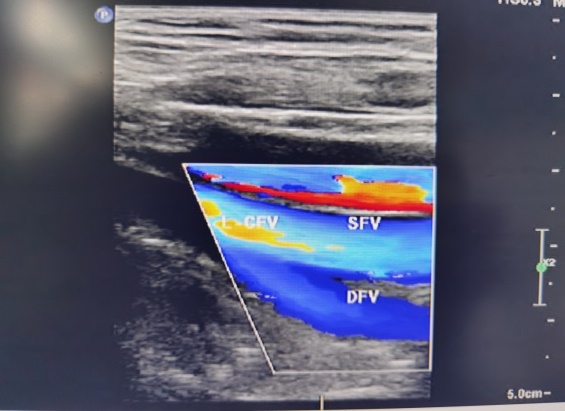

2.超声图像中的红、蓝两色是不是红色代表动脉,蓝色代表静脉?

答:这种说法是错误的,彩超检查中的红、蓝两色代表的是血流的方向,朝向探头流动的显示为红色,背离探头的显示为蓝色。